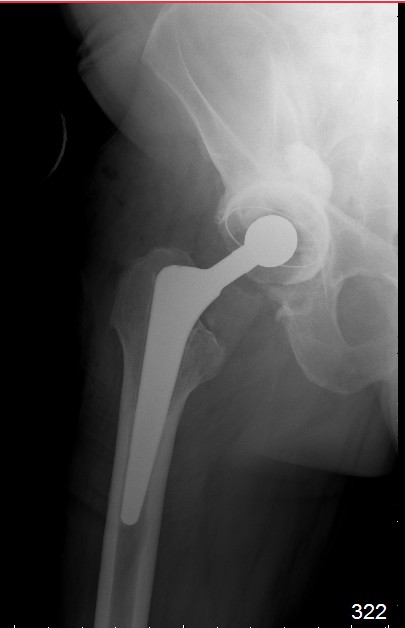

С последним, третьим снимком он ко мне и обратился, после чего он был и прооперирован на правом  тазобедренном  суставе!

Имя     : 0541.jpg